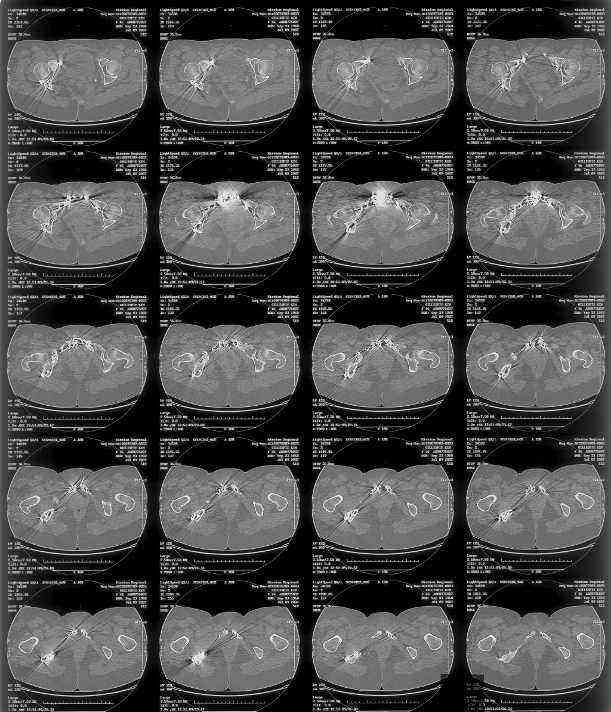

I can't see the axial CT images well enough to detail the potential sacral issues....can you magnify them?

Here is a magnified view. Sorry about the quality but the CT was scanned into our system.

dave